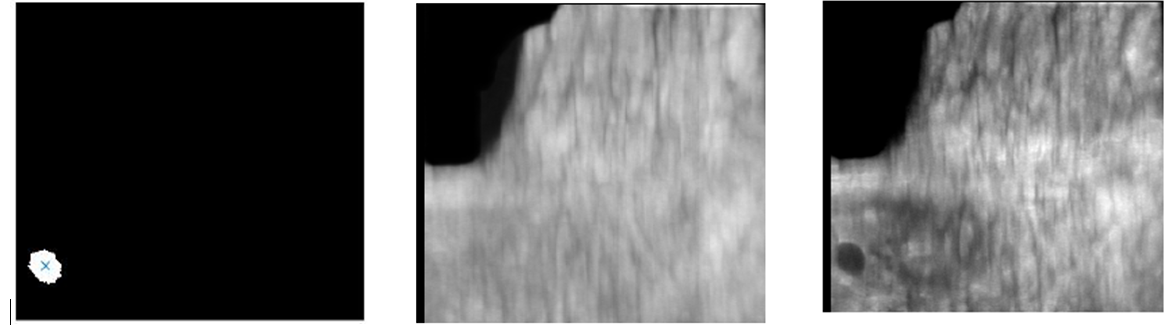

• To develop and evaluate cancer detection and segmentation and lesion follow-up in temporal studies to assess lesion changes over time in ABUS. The figure shows the lesion segmentation framework in ABUS

To obtain images that enhance and focus on the relevant diagnostic information while minimising the amount of redundant information without clinical value. The following image shows an smart projection of an ABUS volume (right) where the lesion is clearly highlighted, in comparison with a conventional intensity projection (center). The lesion location is shown on the left.